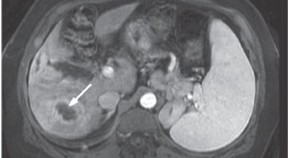

• In this Case Study, Schnitzbauer et al. describe the case of a 30-year-old male who suffered multiple fractures and extensive internal injuries, including liver rupture with formation of a hematoma, because of a motorcycle accident. While in intensive care, the hepatic hematoma became infected with antibiotic-resistant bacteria and serum levels of cholestatic parameters started to increase, until retrograde cholangiography supported a diagnosis of cholangitis in a critically ill patient. Acute liver failure ensued, and liver transplantation carried out. In spite of a number of intervening complications, 50 months after transplantation the patient was in good health; therefore, the authors conclude that post-traumatic sclerosing cholangitis should probably become an indication for liver transplantation.

• Andreas A Schnitzbauer

• Tung-Yu Tsui

• Aiman Obed